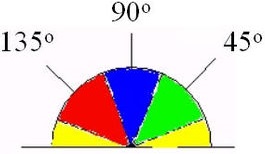

Для обнаружения границ сосуда используется классический подход (edge detection by gradient) совместно с поиском пути. Схема:

Далее нам потребуются направление градиента

3. Направление градиента переводим в градусы или радианы:

4. Выполняем подавление немаксимумов. Если значение градиента